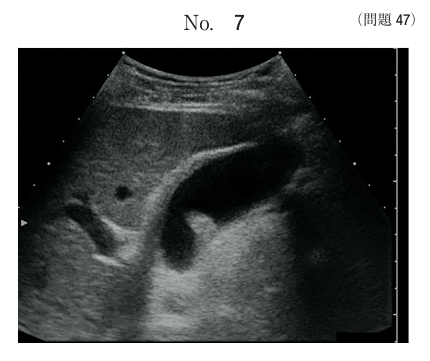

午前/問題47

胆囊病変の超音波画像において考えられる所見はどれか。

1.結石

2.胆泥

3.胆囊炎

4.腺筋腫症

5.コレステロールポリープ